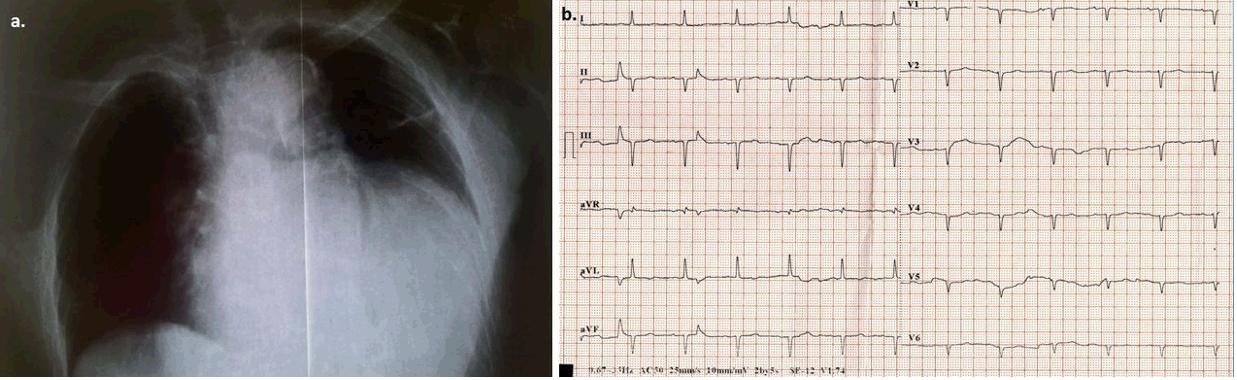

On admission, the patient was haemodynamically stable without fever, or chest pain. Laboratory tests showed high white blood cells (WBC) of 18.000 K/μL, an elevated level of C-reactive protein (CRP) of 5.4 mg/dL (normal limit: 0.08–0.8 mg/dL) and erythrocyte sedimentation rate of 3 mm in the first hour. The chest X-ray (Fig1a) showed a possible pericardial effusion, which was an incidental finding. The patient was referred to emergency bedside echocardiography, which revealed a massive pericardial effusion without evidence of cardiac tamponade, normal left ventricular systolic function and normal wall thickness with ejection fraction of 60%. Beck's triad was absent. The electrocardiograph (ECG) is shown in Figure 1b. There was no dynamic change from the patient’s baseline ECG.During hospitalisation, the patient was under antibiotic treatment with levofloxacin, while for the possible pericarditis she was under treatment with ibuprofen 600 mg every 8 hours and colchicine 0.5 mg OD according to the European Society of Cardiology (ESC) guidelines4. On the third day, she presented with acute kidney failure, which was considered drug-induced and ibuprofen and colchicine were replaced with prednisone 30 mg intravenously OD (0.50 mg/kg/day)4. WBC and CRP decreased gradually and were within the normal limits on the sixth day of hospitalisation. Virological blood tests for herpesviruses (cytomegalovirus, Epstein–Barr virus), enteroviruses (echoviruses, coxsackieviruses), adenoviruses, parvovirus and human immunodeficiency virus were negative. Mantoux tuberculin skin test for tuberculosis was also negative. Rheumatoid factor, anti-nuclear antibodies and anti-neutrophil cytoplasmic antibodies were negative. Thyroid hormones were consistent with subclinical hypothyroidism: TSH 30.25 mIU/L (normal limits: 0.25–3.43); free thyroxin 4 0.81 ng/dL (normal limits: 0.7–1.94). Thyroid antibodies were: anti-thyroid peroxidase antibody >1000 IU/mL (normal limit: <5.61) and anti-thyroglobulin 2.79 IU/mL (normal limit: <4.11).

Figure 1: a. Front chest X-ray demonstrates marked enlargement of the cardiac outline. b. Electrocardiograph (ECG) on admission. Sinus rhythm (~85 bpm), left axis deviation, Q-waves in leads II, III, and poor progression of R-waves in the precordial leads, flattened T-waves in all leads, low QRS voltage in all precordial leads. There was no dynamic change from the patient’s baseline ECG.